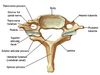

Identify 4 characteristics of the cervical vertebrae

- Bifid spinous process (except C7)

- Transverse foramina

- Large triangular vertebral foramen

- Small & broad body

State 2 functions of the foramen transversium in the cervical vertebrae

- Conduit for vertebral artery (except C7)

- C7 foramen transmits the accessory vertebral vein

Identify 3 characteristics of the thoracic vertebrae

- Demi-facets on vertebral body (whole facets T9-10)

- Costal facets on transverse processes (except T11-12)

- Small circular vertebral foramen